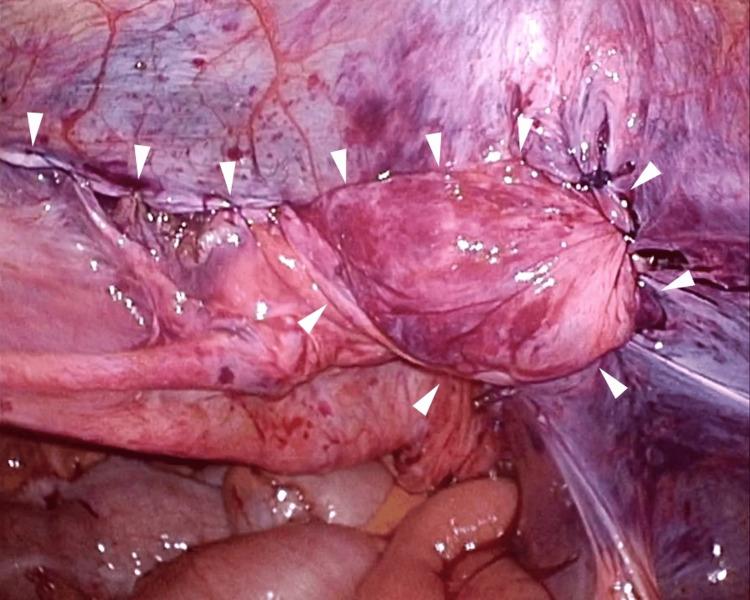

Here, we report a case of laparoscopic trans-inguinal hernia repair (transabdominal preperitoneal repair or TAPP) for a recurrent inguinal hernia following direct Kugel surgery. A 71-year-old man underwent direct Kugel hernioplasty for a right inguinal hernia at another hospital 4 years prior to presentation. The patient subsequently underwent laparoscopic surgery using the TAPP technique, during which the abdominal cavity was visualized with a laparoscope, revealing a tubular mesh protruding towards the abdominal cavity with a direct and indirect hernia ring. Three months post-surgery, no recurrence was observed.

在此,我们报告一例针对直接Kugel手术后复发性腹股沟疝的腹腔镜经腹股沟疝修补术(经腹腹膜前修补术或TAPP)。一名71岁男性在就诊前4年于另一家医院接受了右侧腹股沟疝的直接Kugel疝修补术。该患者随后接受了使用TAPP技术的腹腔镜手术,术中通过腹腔镜观察腹腔,发现一个管状补片向腹腔突出,伴有直疝和斜疝疝环。术后三个月,未观察到复发。